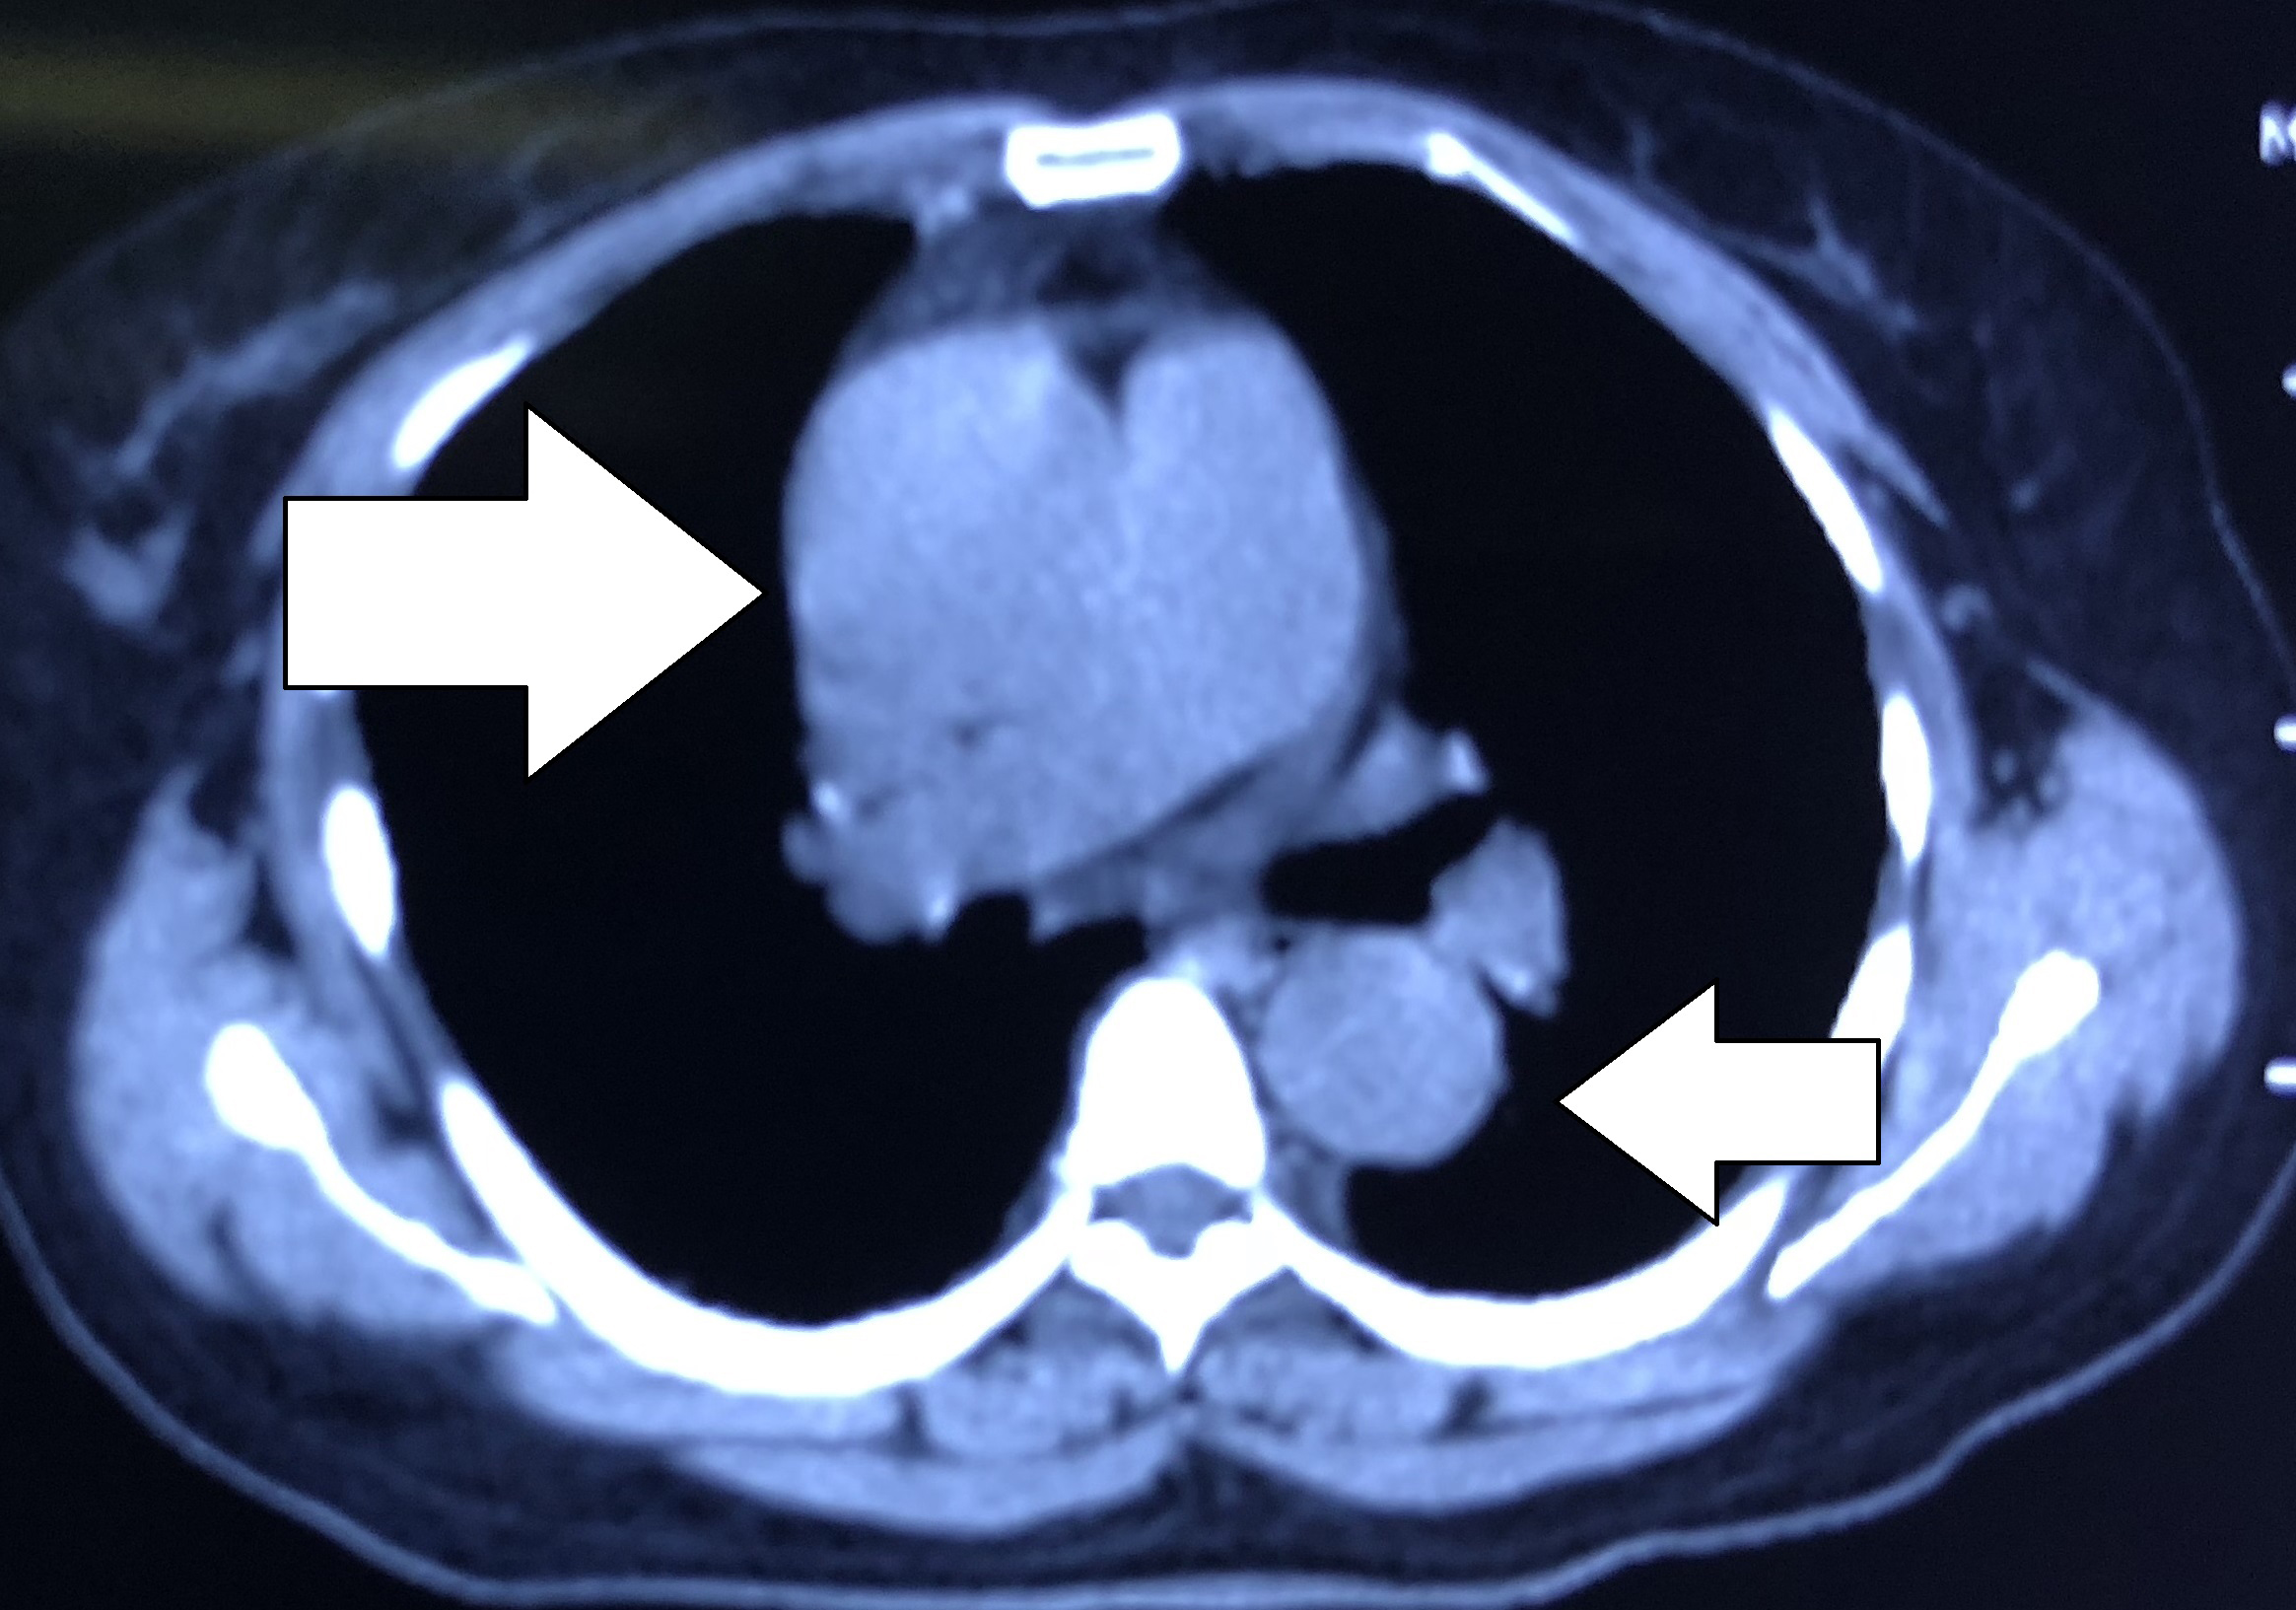

的确很奇怪,这样的描述竟然和主动脉走形如此类似。“病人的心肌酶结果出来了,都在正常范围之内,心电图给你看。”护士把心电图递给我,全导联心电图没有心肌梗死的特征性的表现。难道是夹层?!尤其是病人描述的疼痛变化,几乎就是主动脉走形的素描。摸摸患者的双侧足背动脉,搏动一致,再看看患者的CT,仔细的研读一下,我大吃一惊。患者升主动脉内血液的密度明显不均一,仔细看看降主动脉内似乎有一飘带。难道是夹层?!这一疾病起危险程度远甚于急性心肌梗死。

和患者家属仔细说说病情,目前离患者症状发作已经超过11小时了,但是心肌酶仍然不高,心电图也没有特征性的变化,基本可以排除心肌梗死了,但是有高血压病史(虽然血压似乎不是很高),这再加上疼痛发生的整个过程,还有CT表现,几乎是教科书式的主动脉夹层。然而跟根本不懂医学的家属讲病情还是需要耐心还有化复杂为简洁的能力。和家属交往久了,慢慢就会和患者家属交流了,很快家属就明白了问题所在,同意做强化CT来明确诊断。

在放射科配合下,很快CT片就摆在我们面前了,看着CT我再一次感觉“如履薄冰如临深渊”,如果就按照心肌梗死处置,那就是不可挽回的灾难性后果。

后记:急性心肌梗死、急性肺栓塞和主动脉夹层,这三种疾病构成了高危胸痛最主要的疾病谱。在急诊,在抢救室,诊断和鉴别诊断异常重要,诊断清楚了才会有正确的后续治疗,如果错误的诊断会有灾难性的后果。文中所述CT平扫不能作为诊断的依据,只能是证据的一种,在某些情况下平扫CT可以出现密度不均一,相对于密度不均一,钙化点的内移诊断价值更大。有无高血压、双上肢血压有无差别、足背动脉搏动是否一致,这些都不是诊断主动脉夹层的充分必要条件,所有这些都需要综合病史和疼痛性质来综合考虑。